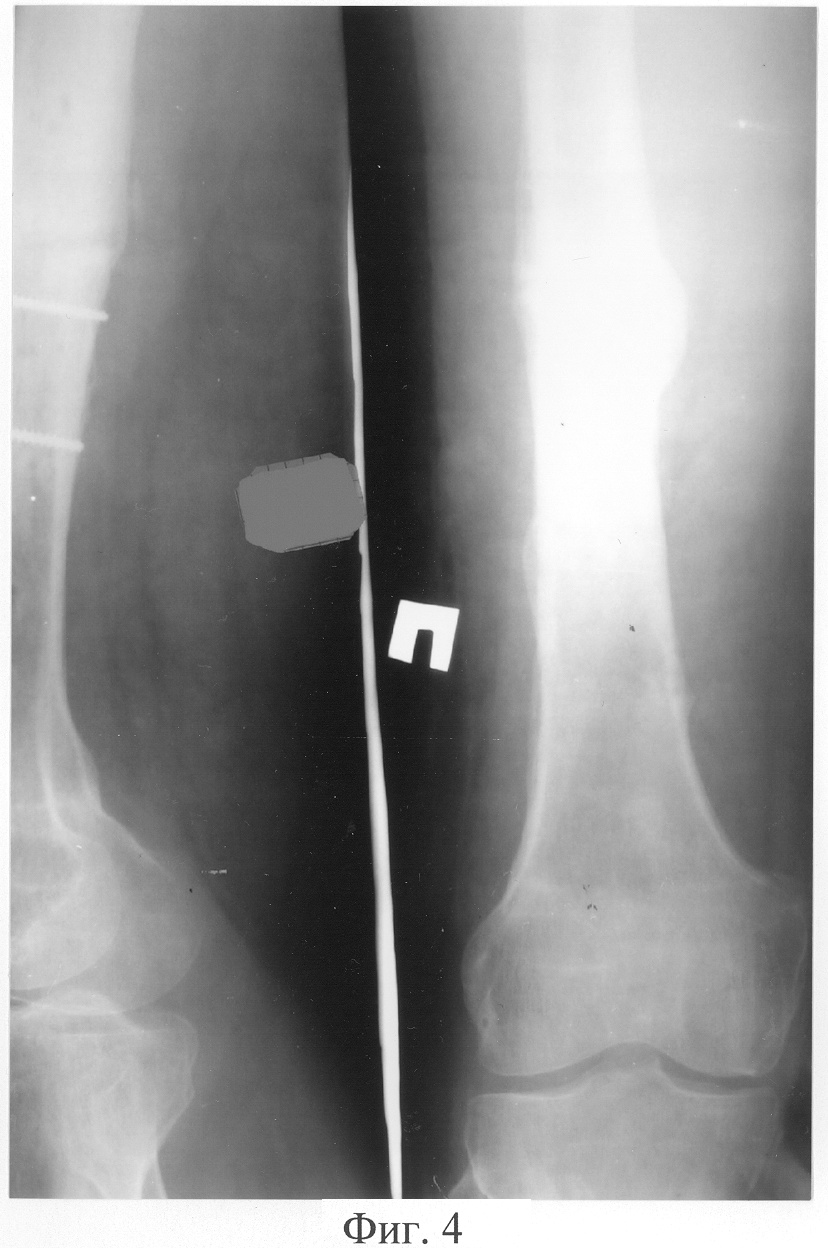

Пример 2. Больной Щ., 28 лет, поступил через 555 дней с момента травмы с диагнозом «Посттравматический псевдоартроз средней трети диафиза правой бедренной кости. Состояние после остеосинтеза металлической пластиной». Из анамнеза известно, что через 7 дней с момента травмы была выполнена операция – остеосинтез средней трети правой бедренной кости металлической пластиной. В течение всего срока лечения беспокоил болевой синдром и ограничение функции правой нижней конечности. Через 548 дней после остеосинтеза металлической пластиной сращения перелома не наступило. В результате больной обратился в клинику травматологии и ортопедии. При клинико-рентгенологическом исследовании был выявлен посттравматический псевдоартроз средней трети диафиза правой бедренной кости. Больному оперативным путем была удалена металлическая пластина. Рентгенограмма правой бедренной кости представлена на фигуре 3. Было налажено скелетное вытяжение за мыщелки правой бедренной кости, которое успешно функционировало в течение 15 дней. Затем была выполнена операция – остеосинтез правой бедренной кости аппаратом внешней фиксации стержневого типа. После чего в асептичных условиях стерильным скальпелем в стерильном почкообразном лотке измельчили 5 пластин биоматериала аллоплант для склеропластики до размеров крошки 1×1 мм. В условиях операционной у больного осуществили забор крови из кубитальной вены в объеме 5 мл. Затем аутокровь в объеме 5 мл в асептичных условиях перелили в предварительно стерилизованный флакон, куда добавили измельченный биоматериал аллоплант для склеропластики. Место будущей инъекции обезболили 5 мл 0,5% раствора новокаина. Вышеназванные субстанции перемешали и набрали в одноразовый шприц для инъекций, снабженный иглой Гордеева с диаметром отверстия 2 мм, после чего произвели однократную инъекцию лекарственной взвеси в полном объеме в зону ложного сустава. Послеоперационный период протекал без осложнений. В течение 45 дней ходил с двумя дополнительными опорами, затем – с одной, при этом получал физиотерапевтическое лечение, занимался лечебной физкультурой, посещал сеансы массажа. Период иммобилизации в аппарате внешней фиксации составил 95 дней (нормальные сроки сращения бедренной кости составляют 120-180 дней; в условиях отягощенного анамнеза – например, при ложном суставе, – затягиваются на неопределенный срок). Через 95 дней диагностировано сращение в зоне псевдоартроза, подтвержденное клинически и рентгенологически. Рентгенограмма представлена на фигуре 4. Осложнений в процессе лечения не было. Получен хороший анатомо-функциональный результат лечения.